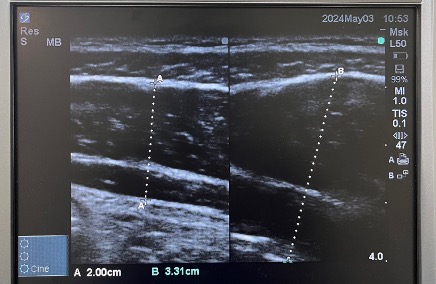

体幹機能検査

超音波エコー検査機器を使って体幹の筋肉(インナーマッスルの状態)が使えているかをお調べします。